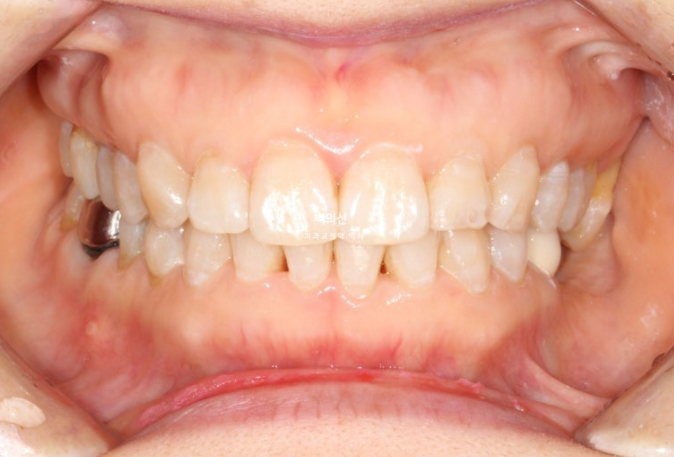

25년 4월부터 7월까지, 4개월간 14개 추가장치를 모두 낀 후 모습입니다.

25.07

교합이 좋지 않으면 치료를 마무리 짓지 않습니다.

유지장치까지 깔끔하게 들어간 모습입니다.

과개교합과 중심선의 개선.

내려오고 튀어나와 있던 가운데 앞니는 뒤로 이동하며 돌출감이 줄었습니다

가지런해진 아래 앞니

정돈 된 스마일라인이 돋보이네요

앞니돌출은 개선되었습니다.